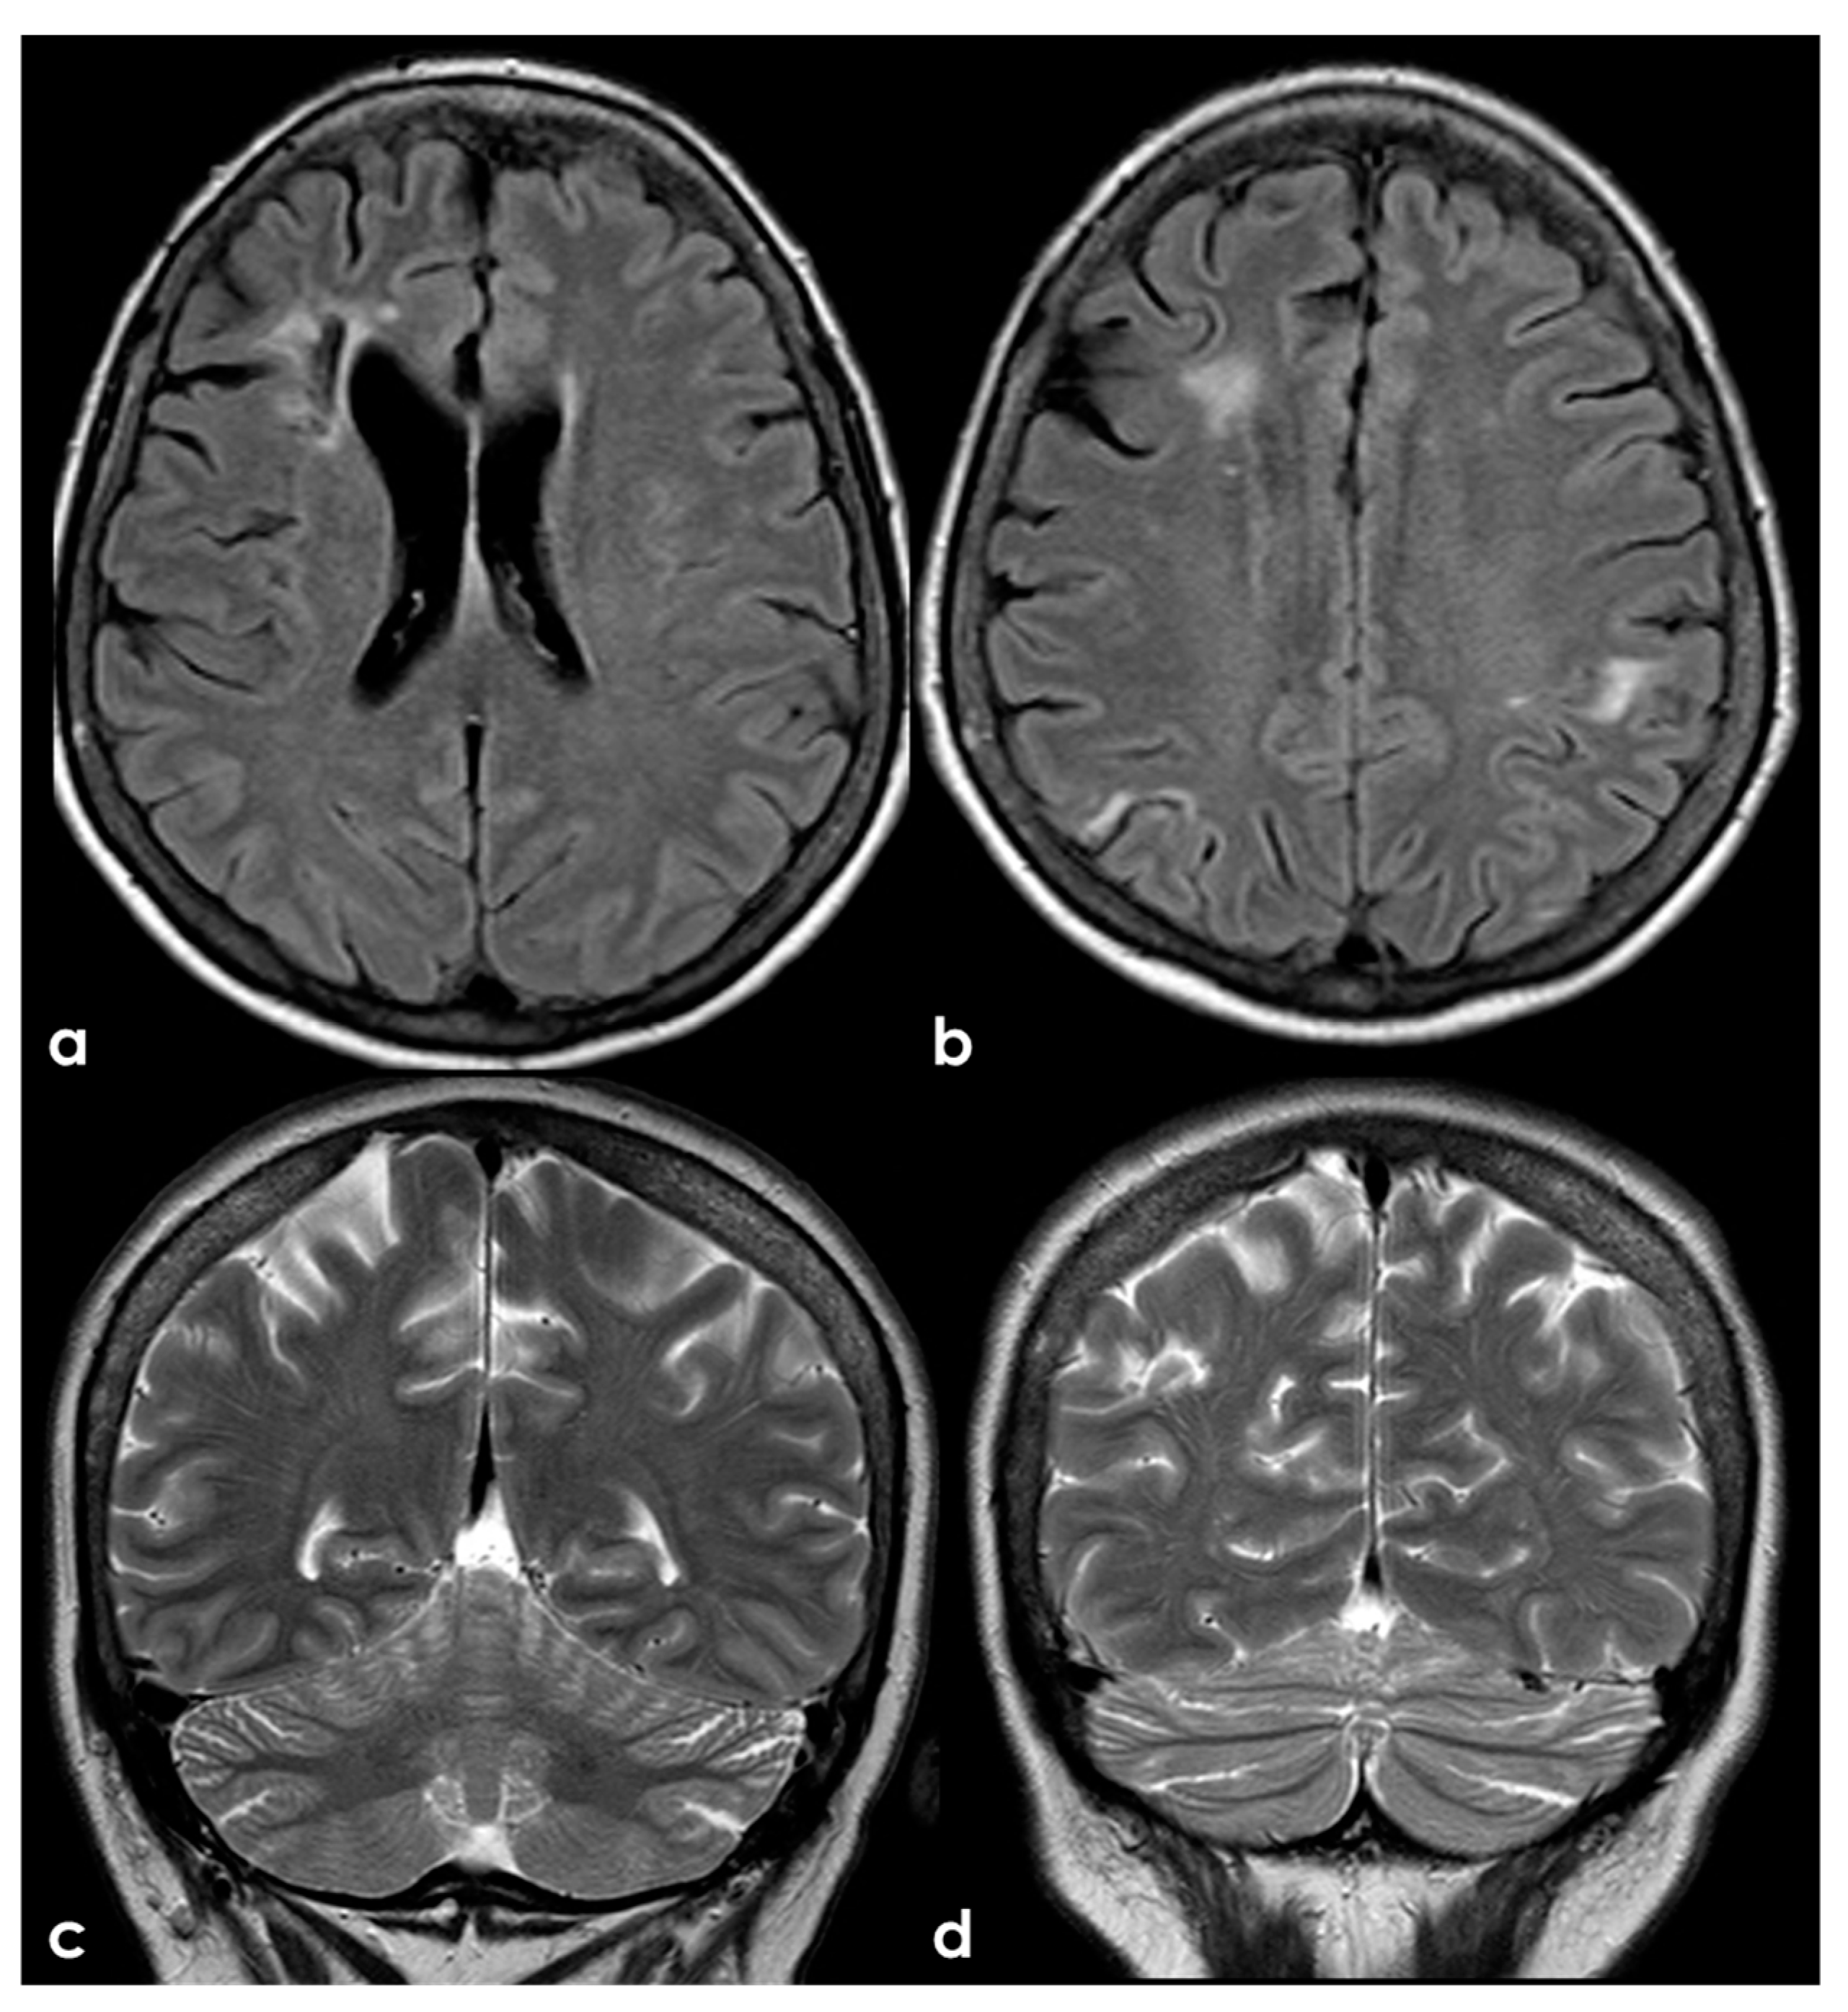

4.2.1. Small-Vessel Disease